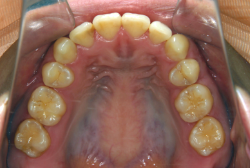

叢生(そうせい)

凸凹な歯並びのことを叢生といいます。矯正歯科に来院する患者様の主訴の中で、最も多いのが「配列の凸凹を真っ直ぐにしたい」というものです。歯の大きさと顎の大きさの調和がとれていないことが原因です。

凸凹を主体としたケースの場合、当院の平均治療期間は18ヶ月ですので、このケースは少し長めに経過しました。理由の一つは凸凹の程度がかなり重症だったと言うことですが、もう一つは、右下第2大臼歯が45度くらい前傾していたため、それを整直化させるために時間を要したと考えています。いずれにしても最終結果は大変よい状態と思います。

治療前は並びが乱れて見た目が悪いというのはもちろん問題ですが、歯科医学的に一番困るのは噛み合わせが悪いという点です。上下の犬歯(3番目の歯)は、上下的に離れた位置にあるため接触することができません。つまり歯としては存在していても、歯としては機能していないということです。